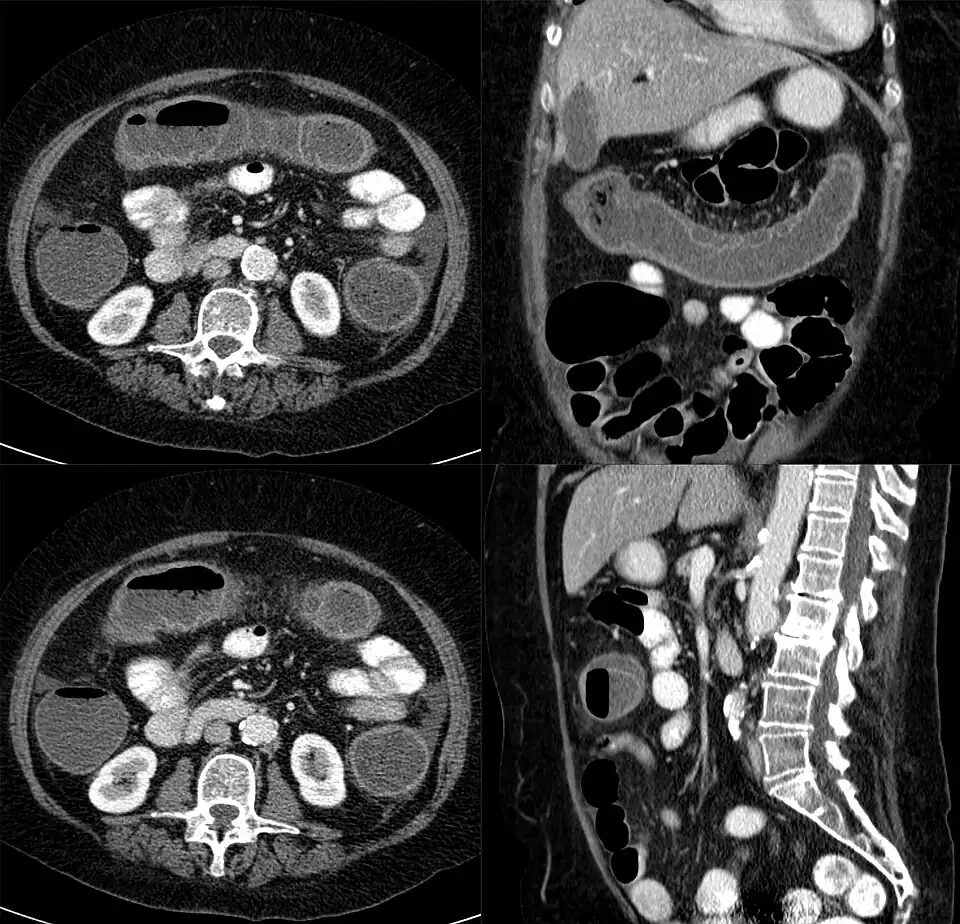

arriba: colon transverso (en corte longitudinal).

derecha: colon ascendente (en corte transversal).

izquierda: colon descendente (en corte transversal). Tomografía axial computada.